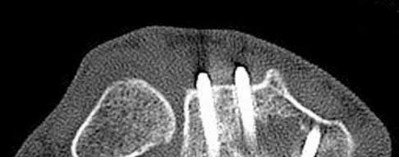

The patient presents with a closed distal third metaphyseal-diaphyseal distal tibia fracture with simple intra-articular extension. Immediate intramedullary nailing along with percutaneous fixation of the articular component provides appropriate restoration of length, rotation and alignment and minimizes the risk of wound complication.

Displaced distal third tibia fractures may be associated with simple intraarticular extension. Operative treatment of intra-articular distal tibia fractures has historically been performed with open reduction and internal fixation. Early open reduction and plate fixation of pilon fractures has been associated with high rates of infection and wound complication. In select patterns with simple articular extension, percutaneous screw fixation and medullary nailing may provide appropriate reduction with minimal soft-tissue risk.

Marcus et al. evaluated the outcomes of immediate intramedullary nailing and percutaneous fixation of simple intra-articular distal tibia fractures (AO/OTA 43 C1 and C2). The authors found excellent rates of union and alignment, however caution against broad application of this technique until more rigorous randomized studies can be performed.

Figures A and B demonstrate a distal third tibial shaft fracture with simple intra-articular extension. The axial and coronal CT cuts in Figures C and D further clarify the articular injury. Illustrations A and B demonstrate a comminuted distal third tibial fracture with simple intra-articular extension. Illustrations C and D are fluoroscopic images of the same injury after intramedullary nailing and percutaneous fixation of the articular component.

A 25-year-old female is involved in a motor vehicle collision. She presents with the isolated injury seen in Figures A through D. Her leg is swollen but her skin is intact. She has no clinical signs of compartment syndrome. Which of the following treatment options will allow for maintenance of fracture alignment and minimize the risk of soft tissue complications?